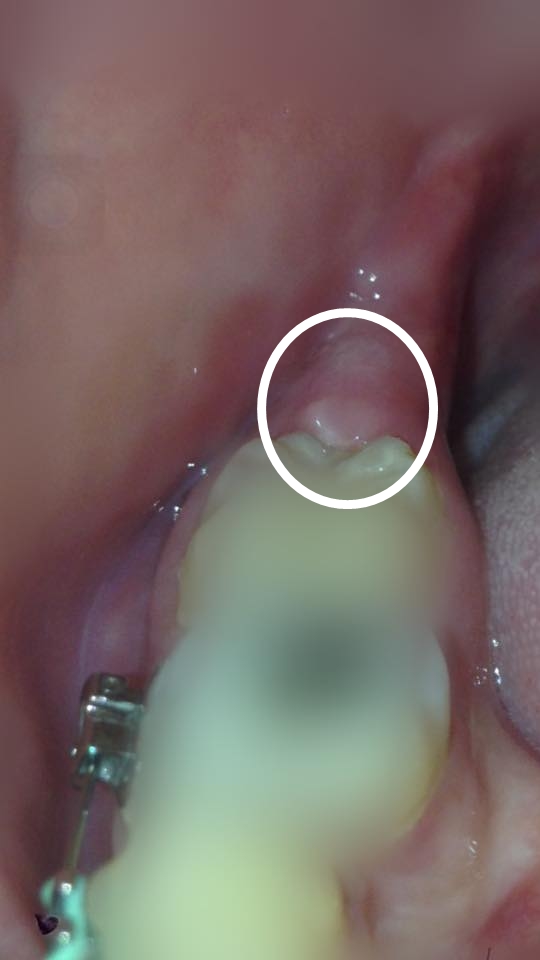

มีปัญหาขณะจัดฟันครับ ช่วยหน่อย

จัดฟันมาได้เกือบปีแล้วครับวันดีคืนดี ฟันที่จัดเริ่มดันฟันกรามซี่ในไปทิ่มเหงือกจนทำให้เกิดแผล

แบบนี้ต้องไปพบคลินิกทำฟันไหมครับ

ฟันเหลือ ขออณุณาติเบลอนะครับ

(ฟันคุดผ่าออกหมดแล้วนะครับ)